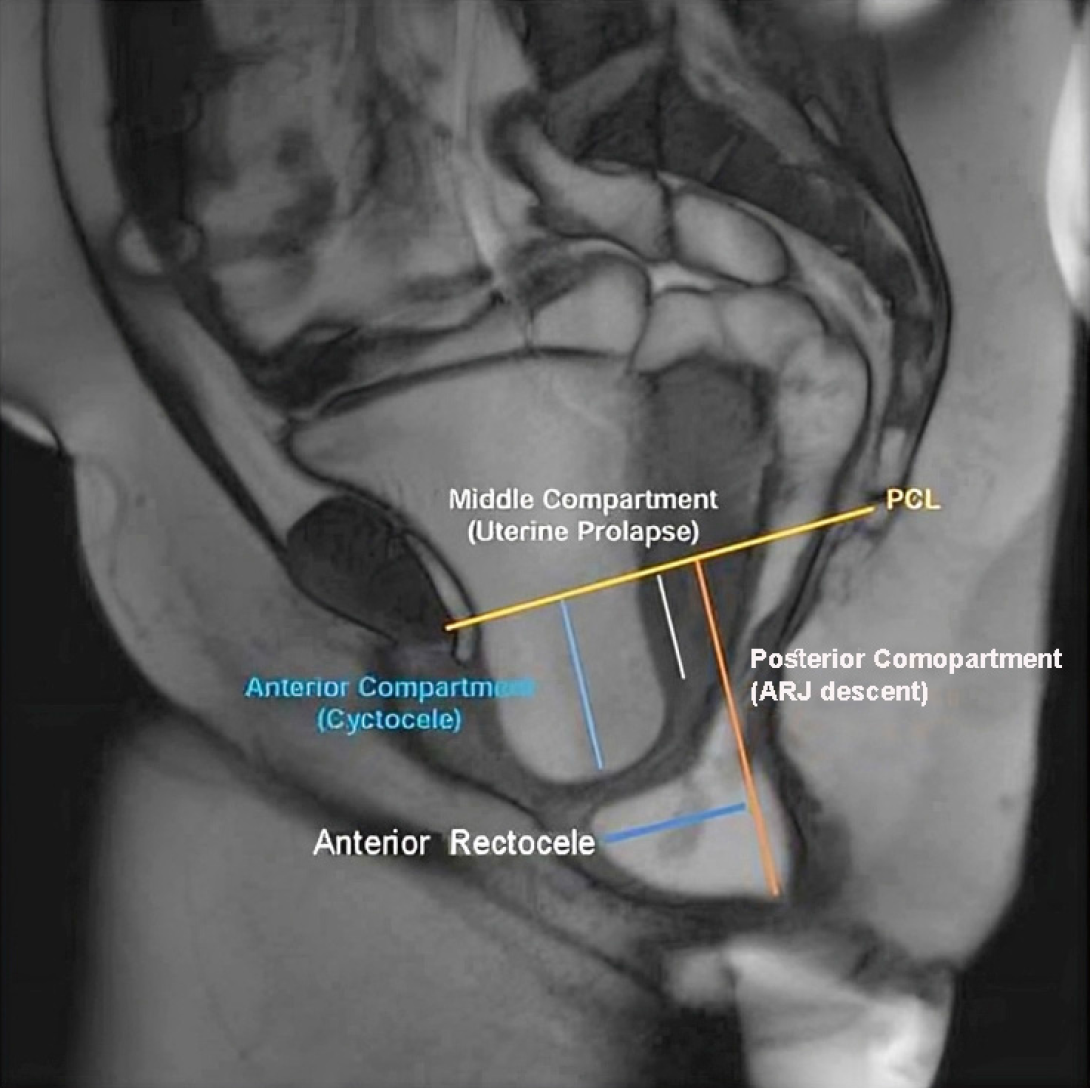

Figure 2 Magnetic resonance defecography image showing pelvic organ prolapse across all three pelvic compartments[15].

Anterior compartment: Cystocele (blue); Middle compartment: Uterine prolapse (white); Posterior compartment (orange, anterior rectocele and anorectal junction descent). Citation: Shetty A, Walizai T, Murphy A. MR defaecating proctography. Radiopaedia 2016. Copyright ©The Author(s) 2016. Published by Radiopaedia[15] (Supplementary material).